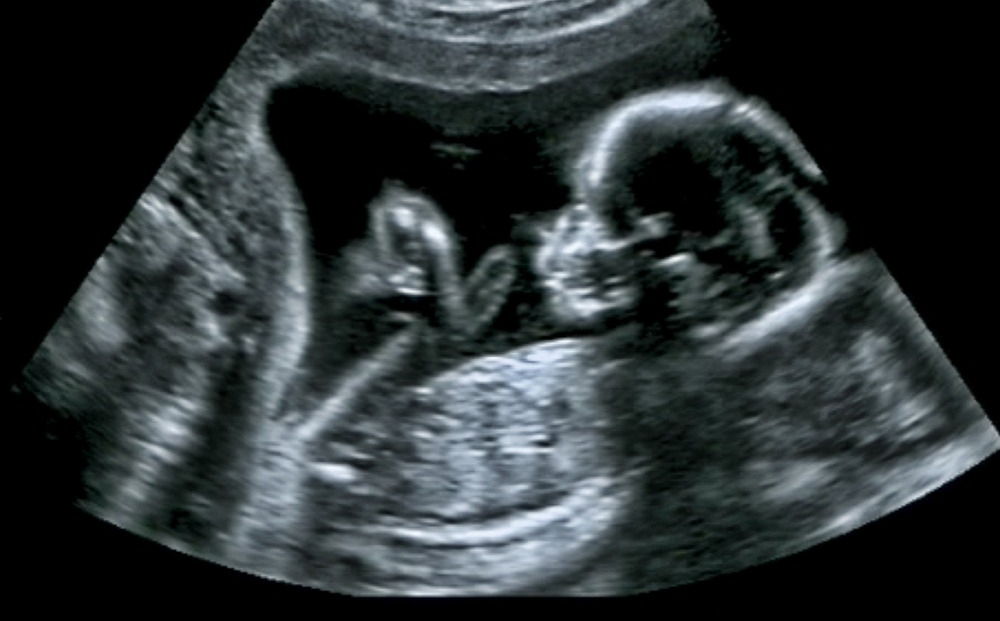

Ένα υγιέστατο αγοράκι γέννησε η 39χρονη Ειρήνη Κόκα, η πρώτη γυναίκα στην Ελλάδα που αποκτά παιδί με μεταμόσχευση ωοθηκικού ιστού. Το βρέφος, βάρους 3 κιλών και 20 γραμμαρίων, γεννήθηκε με καισαρική το Σάββατο 8 Ιουνίου.

Περίπου 1,5 χρόνο μετά την επέμβαση, ωάρια που συλλέχθηκαν από τις ωοθήκες γονιμοποιήθηκαν με σπέρμα του συζύγου της κ. Κόκα.